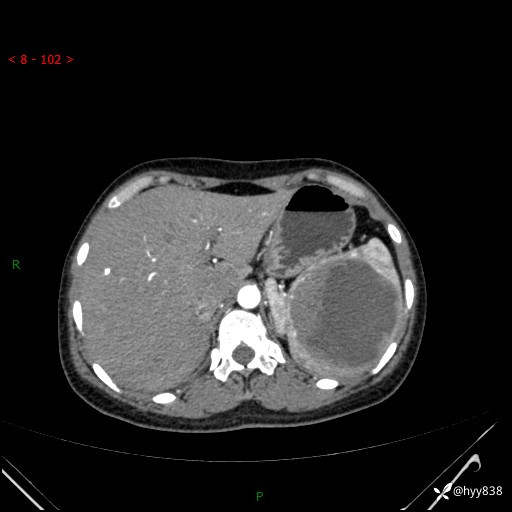

患者性别:男

患者年龄:44岁

主诉:外院超声发现脾脏占位,来我院进一步诊治。

辅助检查:CT

临床诊断:脾脏占位

脾脏CT平扫+增强(动脉期+静脉期)